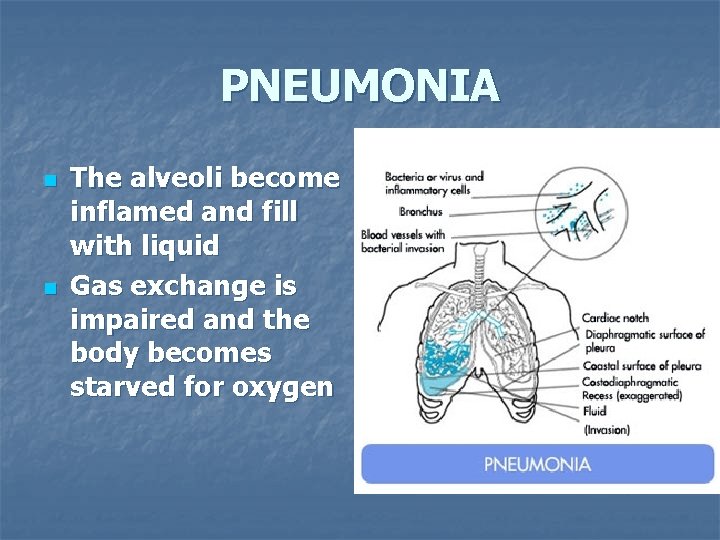

PNEUMONIA n n The alveoli become inflamed and fill with liquid Gas exchange is impaired and the body becomes starved for oxygen